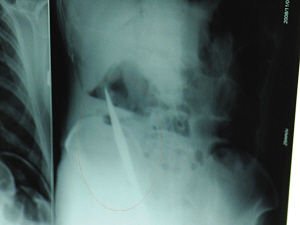

X光片上,尖刀清晰可見(jiàn)。

從男子體內(nèi)取出的尖刀足足有19厘米長(zhǎng)。

6日上午,記者在徐州礦務(wù)集團(tuán)總醫(yī)院重癥監(jiān)護(hù)室見(jiàn)到了這名男子,目前他雖然已經(jīng)恢復(fù)了意識(shí),但還不能開(kāi)口說(shuō)話,需要呼吸機(jī)輔助呼吸。據(jù)醫(yī)生介紹,4日中午12時(shí)左右,這名男子因服毒輕生被緊急送到醫(yī)院進(jìn)行搶救,之前,這名男子已經(jīng)在當(dāng)?shù)剜l(xiāng)鎮(zhèn)醫(yī)院進(jìn)行了近20小時(shí)的治療,但效果不佳!安∪吮晦D(zhuǎn)院到礦總院時(shí)已神志不清,血壓極低,處于休克狀態(tài)!本茸o(hù)人員給男子洗胃、初步處理以后,發(fā)現(xiàn)男子呼吸急促,于是趕緊給他拍片檢查。結(jié)果讓所有的醫(yī)生大吃一驚,竟有一把尖狀異物橫在該男子腹腔內(nèi)!當(dāng)天下午5時(shí)30分,輕生男子被推上了手術(shù)臺(tái)。經(jīng)過(guò)40多分鐘的手術(shù),該男子腹腔被打開(kāi),手術(shù)醫(yī)生發(fā)現(xiàn),男子體內(nèi)的金屬狀異物竟然是一把長(zhǎng)19厘米的尖刀!